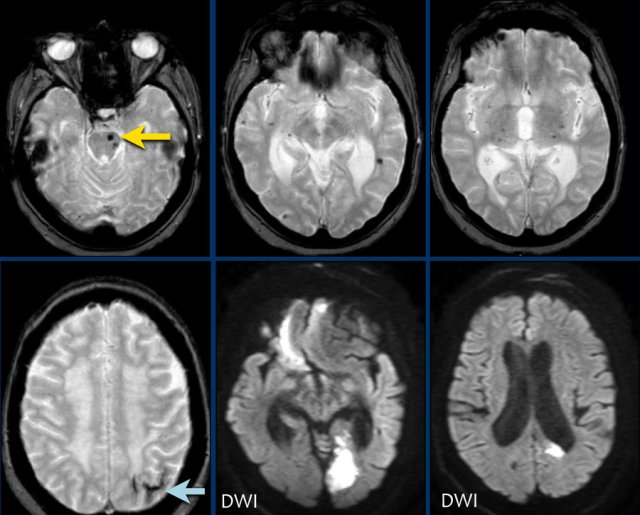

This patient with CAA presented with a large lobar hematoma in the right temporal lobe.

Notice the superficial siderosis (arrow).

This patient with CAA has microbleeds, superficial siderosis and multiple infarcts.

Notice the hemorrhage in the pons (yellow arrow).

There is superficial siderosis in the left occipital region.

The DWI shows infarction in left occipital lobe and reight frontal lobe (with some artifacts).